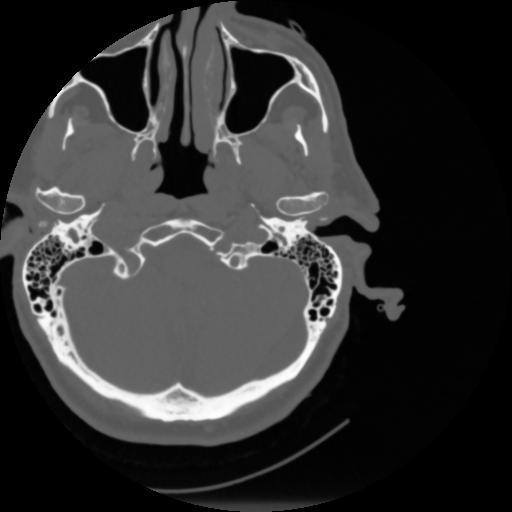

4 CEREBRO,,Vol,0.5,CEREBRO,,